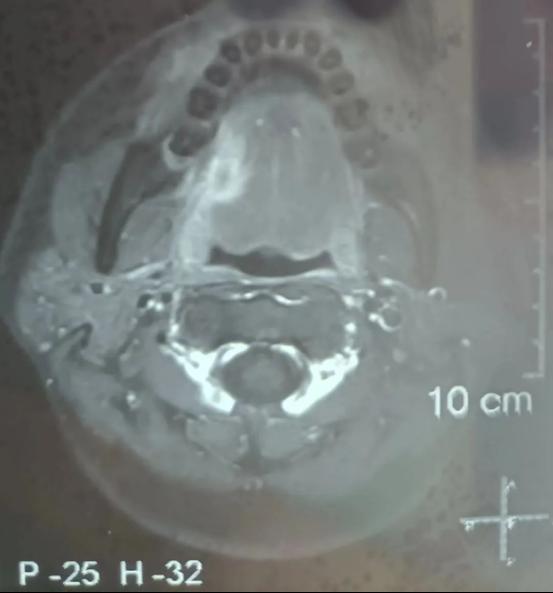

今年34岁的患者因“右舌缘疼痛性包块3+月”到91直播 口腔颌面外科住院治疗,完善病理活检及颌面部MRI检查后明确为右舌缘鳞状细胞癌,临床分期为cT3N0M0,且肿瘤已侵犯右侧舌外肌。

患者颌面部MRI影像